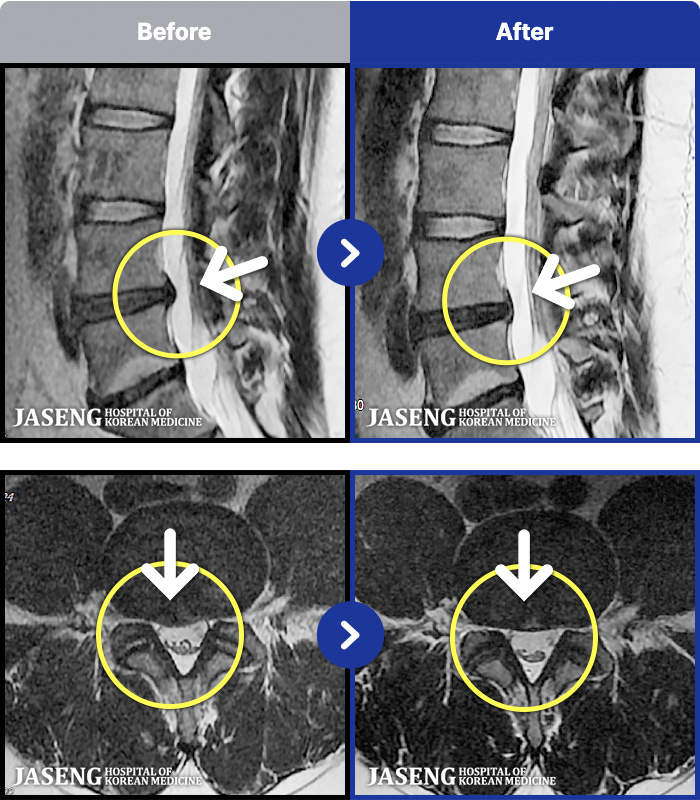

MRI ġ

1,240 MRI ũ ʸ Ȯϼ.